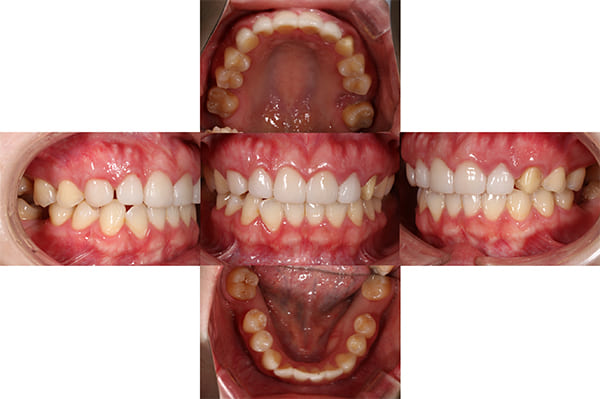

初診時の口腔内

「前歯の歯ぐきの腫れが引かない」と来院された20代女性の患者さまです。

数年前に他院でセラミック治療を受けた後から、歯ぐきの腫れが続いており、なかなか改善しないことを気にされていました。

初診時の口腔内写真からもわかるように、特に前歯の歯肉が赤く腫れ上がっている状態でした。

こちらが最終補綴物を装着した後の口腔内写真です。

初診時に見られた歯肉の炎症は改善し、健康的で引き締まった歯肉へと回復しています。

補綴物も高い透明感と自然な質感を備えており、審美性・機能性ともに理想的な仕上がりとなりました。